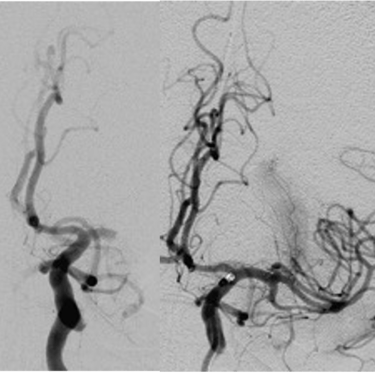

Vaskuläre und endovaskuläre Neurochirurgie

Gehirnaneurysma (Clip, Coil, Flow Diverter)

Arteriovenöse Malformationen

Zerebraler Bypass

Schlaganfall-Thrombektomie